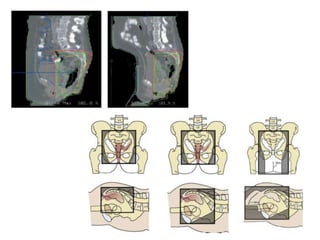

SAGITTAL VIEW CORONAL VIEW

Always check final volumes in sagittal and coronal views to

Rectal Cancer RadiotherapyContouring Guideline for clinical target volumes (CTV) for neoadjuvant chemoradiotherapy in locally advanced rectal cancer: gross tumor, peri-rectal, pre-sacral, internal iliac and external iliac. NTUH practice: • GTV: main tumor mass + involved lymph nodes • CTV: – GTV with 15 mm expansion – Distal 20 mm margin to GTV for CTV – Vessels with 7 mm expansion – Contour CTV to include mesorectum and pre-sacrum – Avoid bone and small bowel Int J Radiat Oncol Biol Phys. 2009 Jul 1;74(3):824-30. doi: 10.1016/j.ijrobp.2008.08.070.

RTOG CONSENSUS PANELRECOMMENDATIONS • Risk volumes defined as CTVs: these were local and nodal. • Local CTV included mesorectum, presacrum, scar tissue and anastomosis. • Nodal CTV included perirectal, iliac (external and internal) and inguinal. • Nodal CTVs: – CTVA: internal iliac, presacral and peri-rectal – CTVB: external iliac – CTVC: inguinal 73 https://www.rtog.org/CoreLab/ContouringAtlases/Anorectal.aspx; Myerson et al. IJROBP 2009

International consensus guidelineson Clinical Target Volume delineation in rectal cancer • Consensus was obtained for delineation of the CTV for elective irradiation of all regional lymph node levels. • Seven subsites at risk were identified: presacral space (PS), mesorectum (M), lateral lymph nodes (LLN), external iliac nodes (EIN), inguinal nodes (IN), ischiorectal fossa (IRF) and sphincter complex (SC). 74 Radiotherapy and Oncology 120 (2016) 195–201 http://dx.doi.org/10.1016/j.radonc.2016.07.017

76 SAGITTAL VIEW CORONALVIEW Always check final volumes in sagittal and coronal views to make that the contoured volume makes sense in 3 dimensions